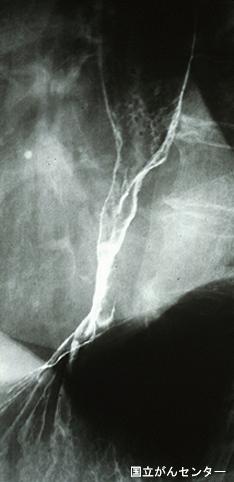

疾病(病理主体)的分类恶性上皮性肿瘤/腺癌

部位(按器官分)食道/下

检查方法X线

肿瘤的肉眼分类3型(溃疡浸润型)/

肿瘤最大直径40以上

肿瘤的深度s(a)